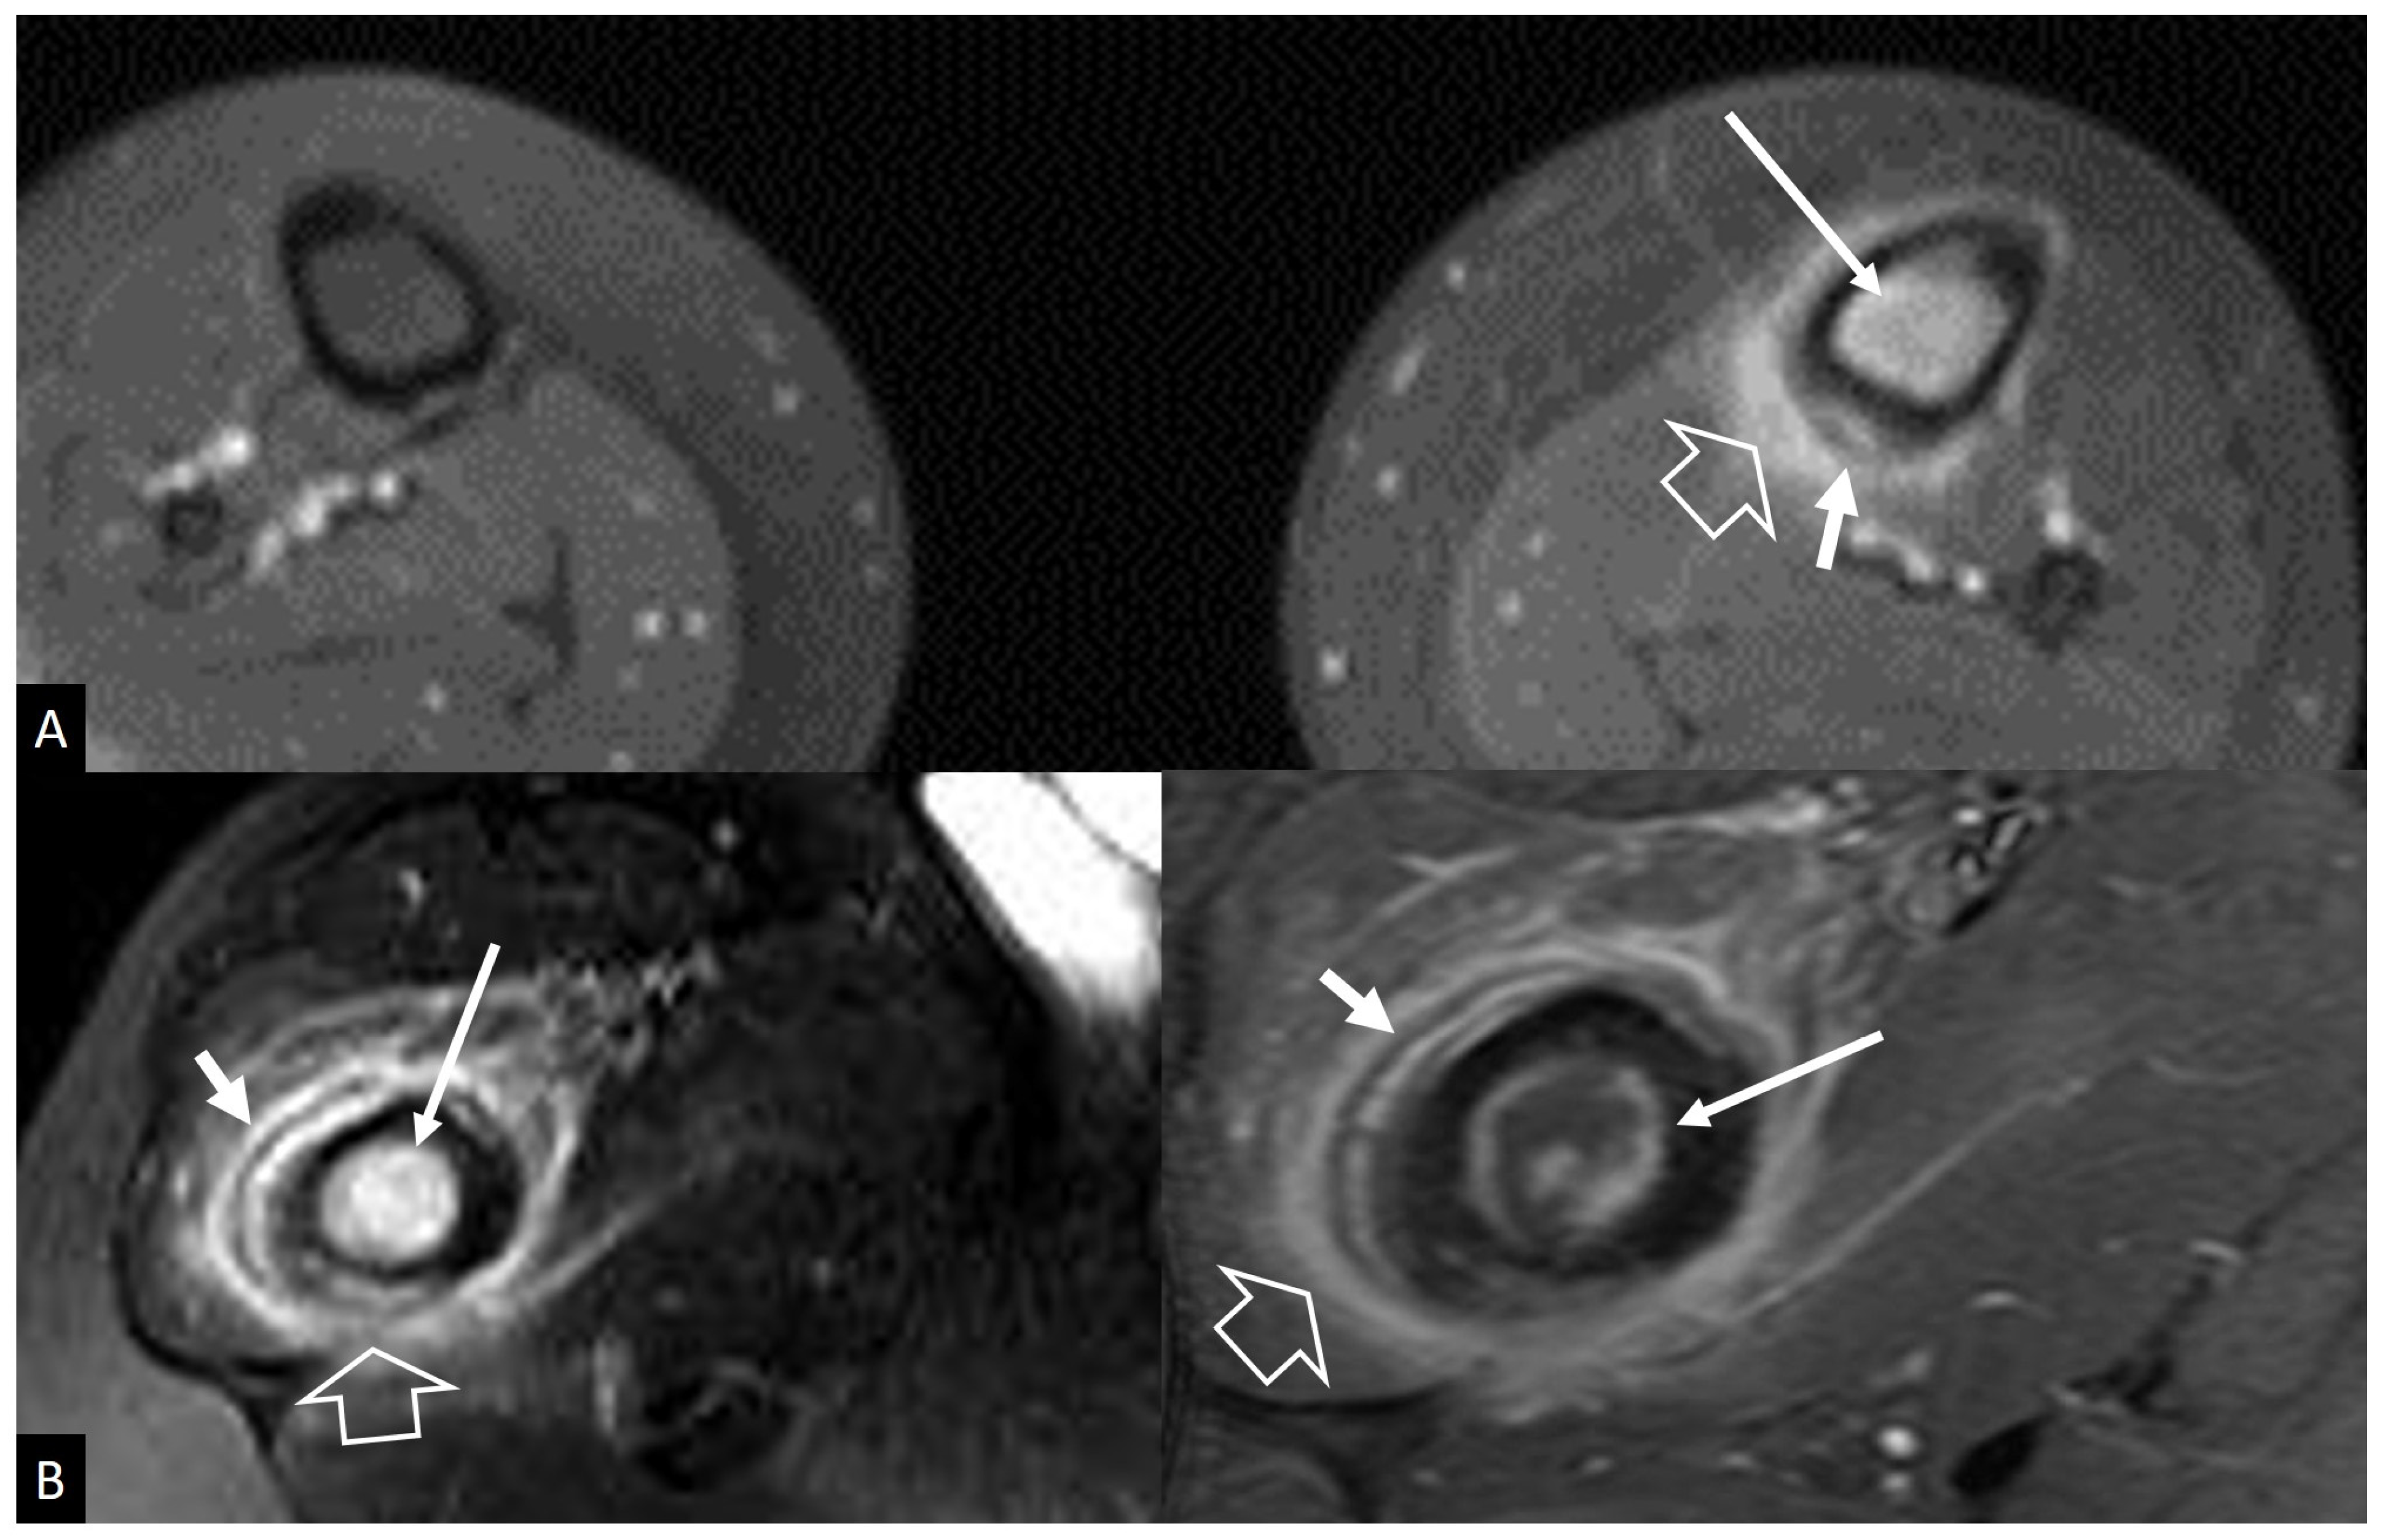

3. Long Bones

3.1. Stress Injuries

3.2. Neoplasms

3.2.1. Ewing’s Sarcoma

3.2.2. Lymphoma